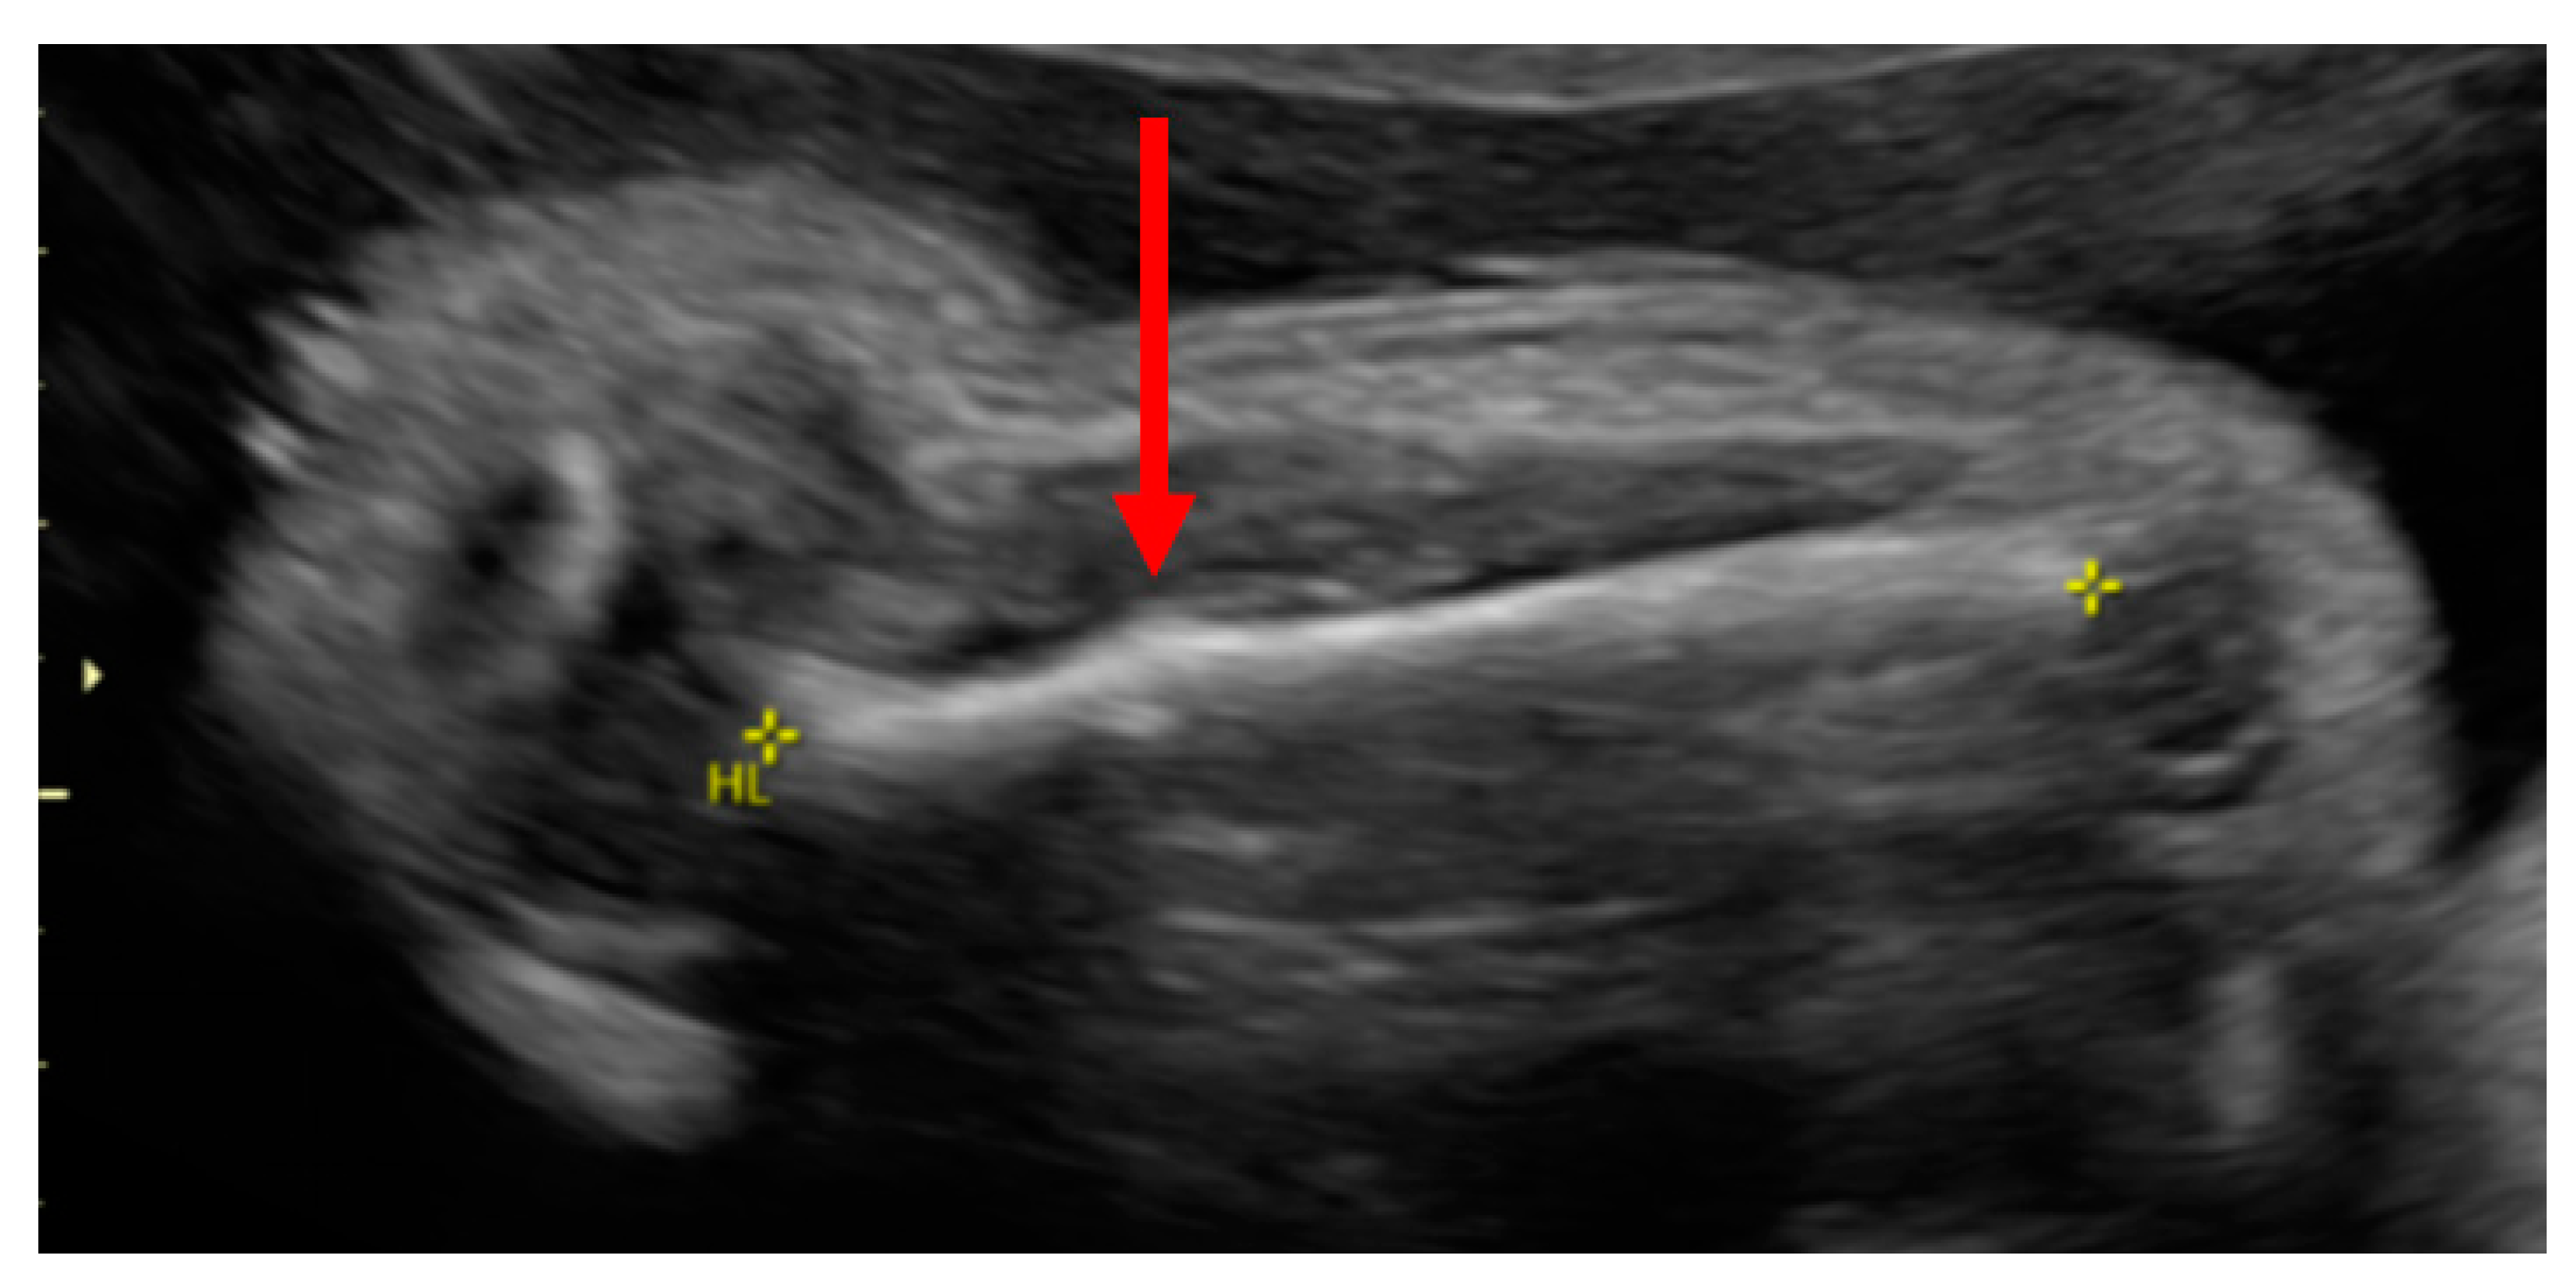

3.1. Phenotypes of the Patient and Parents